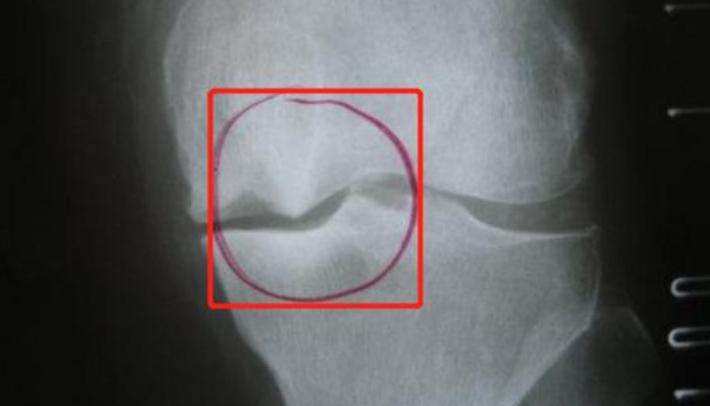

常见的有踝关节(脚部跟骨)附近的骨刺、膝关节半月板附近的骨刺、脊柱骨刺等等。

膝关节的骨刺,可能会引起膝盖痛、膝盖活动时有响声等表现。甚至造成骨关节的炎症。